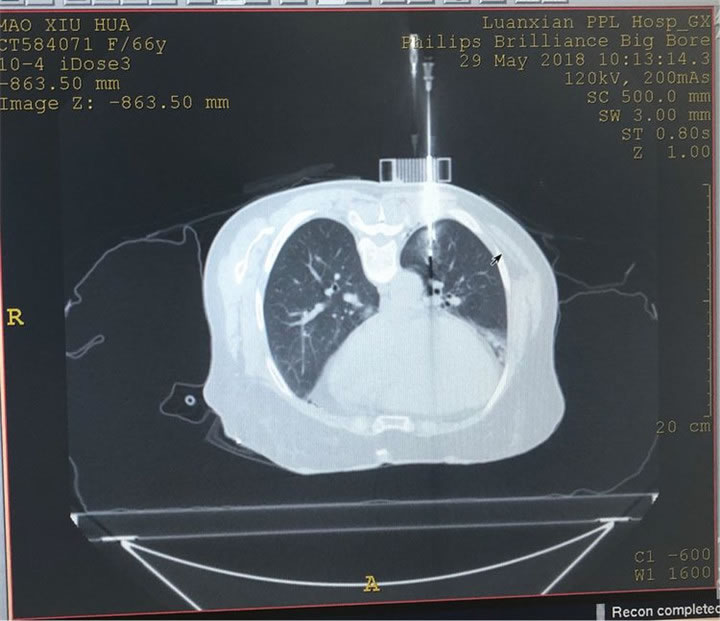

同軸套管針插植

同軸套管針一次插植到位